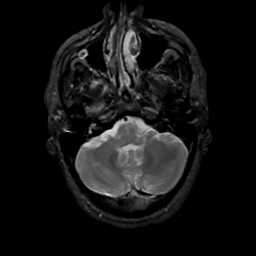

MR Study #4, March 3, 1991 -- Slice #10

[Home][Help][Clinical][Tour 1][Tour 2] Slice 10